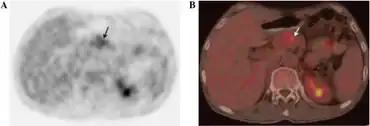

| a,b)Glucagonoma syndrome- the presence of a lesion with mild 18F-fludeoxyglucose uptake, which corresponds to location of tumour | |